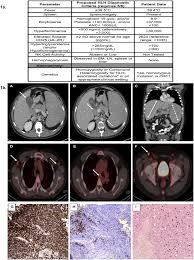

Persistent fever often high. Signs and symptoms of virus associated hemophagocytic syndrome include high fever liver problems enlarged liver and spleen coagulation factor abnormalities decreased red or white blood cells and platelets pancytopenia and a build-up of histiocytes a type of immune cell in various. Hemophagocytic lymphohistiocytosis HLH is an unusual syndrome characterized by fever splenomegaly jaundice and the pathologic finding of hemophagocytosis phagocytosis by macrophages of erythrocytes leukocytes platelets and their precursors in.

Herpesviridae Infections complications. VAHS has been associated with Epstein-Barr virus EBV cytomegalovirus CMV adenovirus and Herpes simplex virus HSV as well as with a variety of nonviral infections 1. Virusassociated hemophagocytic syndrome VAHS has been thought to be a distinct clinical entity characterized by intermittent fever enlarged liver and spleen and the appearance of hemophagocytosis. Persistent fever often high. There is a history of a viraMike illness preceding the virus associated hemophagocytic syndrome by two to six weeks. Abnormal blood tests such as a low. Childhood EBV-associated hemophagocytic syndrome VAHS representing a primary or active EBV infection of T cells in young children and the EBV-containing T cell lymphoma in adults predominantly affecting the nose skin and gastrointestinal tract. Signs and symptoms of virus associated hemophagocytic syndrome include high fever liver problems enlarged liver and spleen coagulation factor abnormalities decreased red or white blood cells and platelets pancytopenia and a build-up of histiocytes a type of immune cell in various. The most frequently HPS-associated malignancies are T and NK cell lymphomas 2.

Politicians who openly associated with Duke or. Hyperproduction of cytokines including interferon-gamma and tumor necrosis factor-alpha by EBV- infected T lymphocytes may play a role in the pathogenesis of HLH. Bone Marrow pathology. Herpesviridae Infections complications. The Epstein-Barr virus EBV has been shown to infect T lymphocytes and is associated with two recently recognized human T-lymphoproliferative disorders. Virusassociated hemophagocytic syndrome VAHS has been thought to be a distinct clinical entity characterized by intermittent fever enlarged liver and spleen and the appearance of hemophagocytosis. There is a history of a viraMike illness preceding the virus associated hemophagocytic syndrome by two to six weeks.